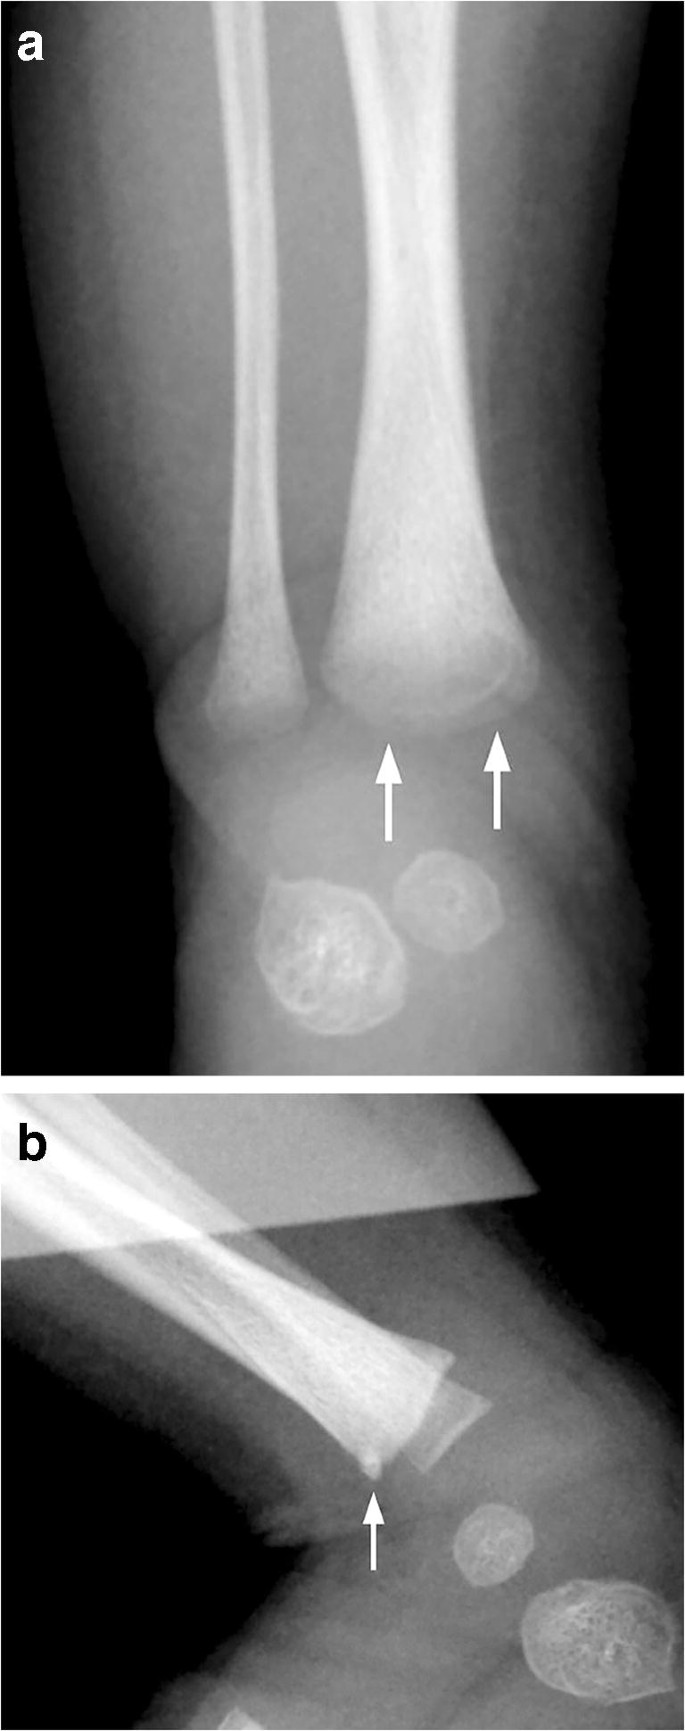

radiological dating of fractures and even less relating fractureagetochildabuse . Themostcomprehensivereview is byO'ConnorandCohen .' . . . Fresh fractures , including metaphyseal fractures , have sharply defined margins . With the development of an osteoclastic response to necrotic bone the fracture ends

These metaphyseal abnormalities were identified from postmortem radiogra-phy and correlated with microscopy . The au-thors concluded the metaphyseal alterations represented partial or complete planar micro- fractures that transected the primary spongio-sa adjacent to the growth plate . These micro- fractures usually resembled a "bucket-handle"

Specific fractures . A number of fractures have been recognised as highly specific to non-accidental injuries (rather than accidental injury) . They include: metaphyseal fracture (so-called bucket handle fracture or corner fracture ) present in up to 39-50% of abused infants <18 months; said to be virtually pathognomonic of NAI; rib fractures